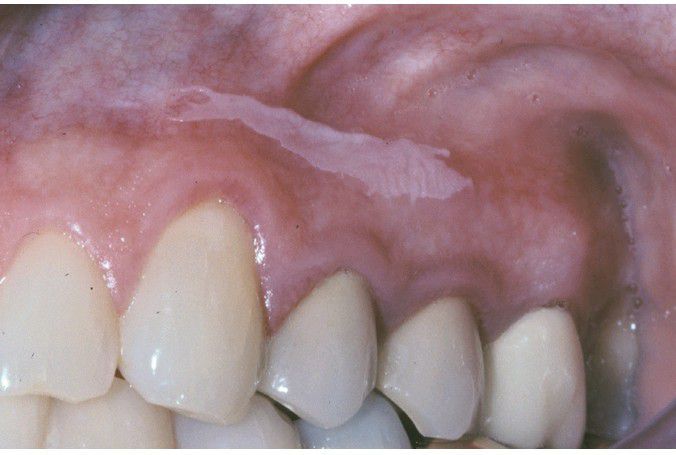

Sanguinaria-associated Keratosis

. Thin white plaque on the maxillary alveolar mucosa.